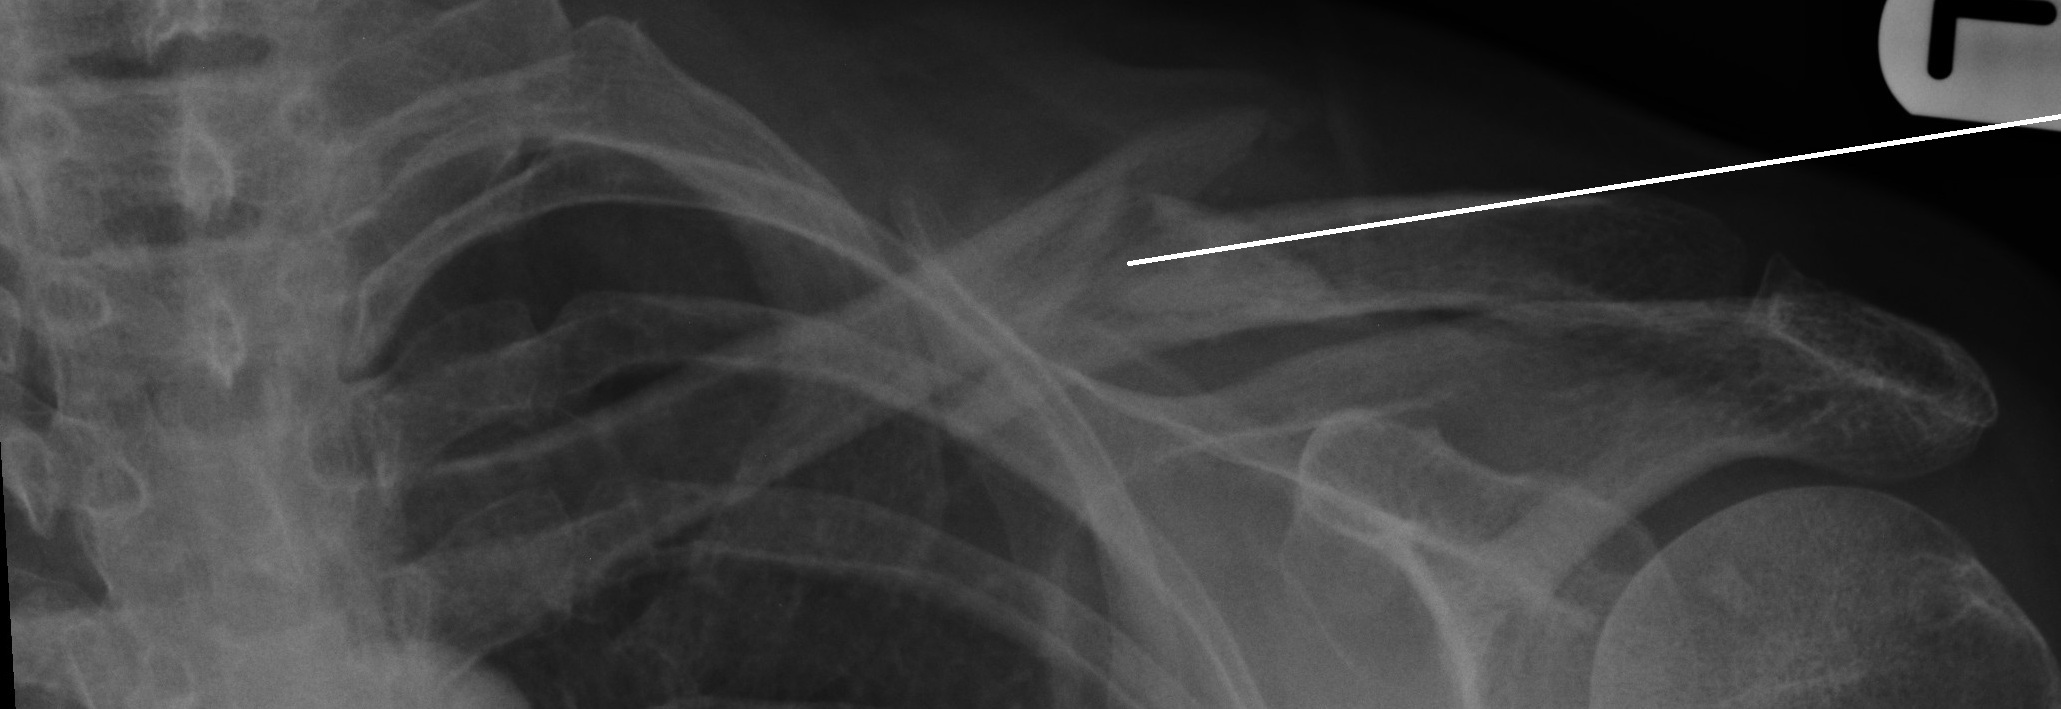

A multi-fragmentary fracture of the clavicle